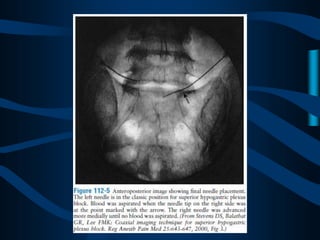

ABORDAJE CLASICO

DE DOS AGUJAS